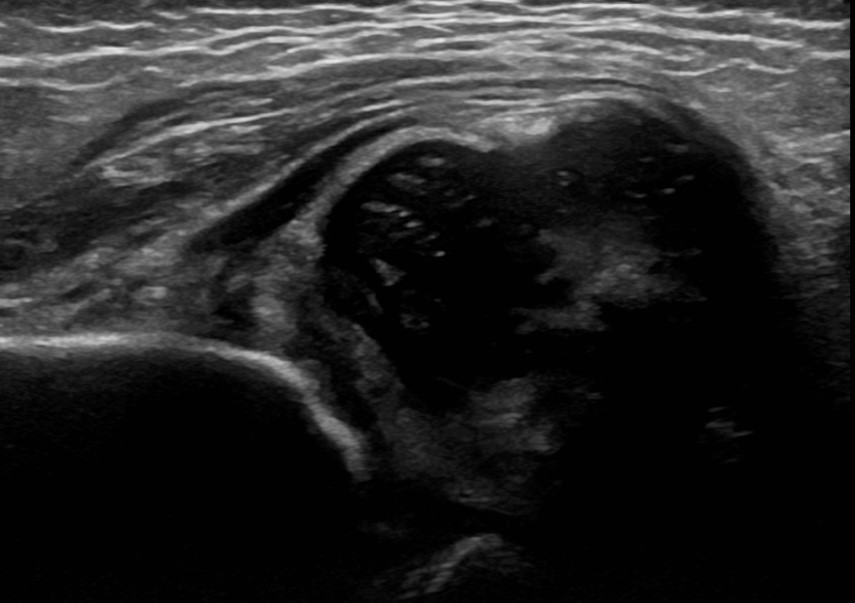

Dislocated hip on ultrasound